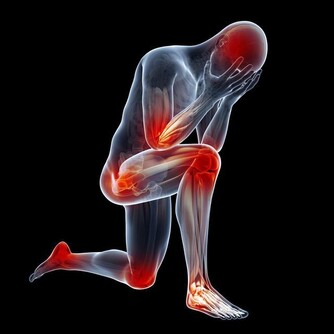

|  血管,一條都不能堵! 必須每天清除「血垢」。家中的自來水管,用的時間長了,管道內壁就要結垢、生鏽,逐漸導致管道受阻而無法供水。

血液中的「血垢」是指膽固醇、甘油三酯等,它們在血管壁上越積越多,形成如同黃色小米粥樣的斑塊。